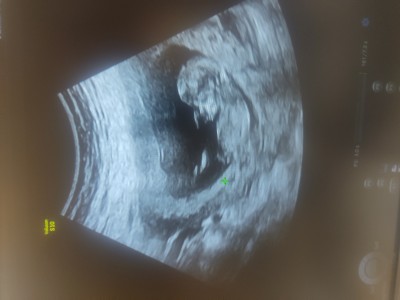

Merhaba kizlar Nub teorisinden anlayan bakabilir mi ? Cinsiyet tahmini :)

Gebelik haftası 12+4